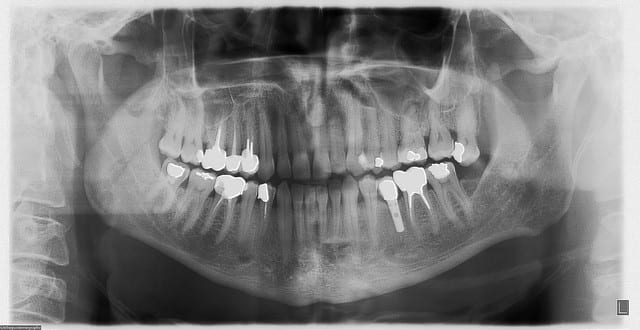

Si la connexion conique ça ne sert à rien, qui peut nous montrer une radio d'implant avec une connexion autre, en fonction depuis quelque temps, et qui ait de l'os à la même hauteur que la connexion ?

http://www.implantdirect.com/us/pop-out/ScrewPlant_Tour_HiQ.htm

c'est pas une connexion conique...

première radio à la pose en 2007

deuxième en 2013....

enfin tout çà pour voir qu'en 6 ans çà n'a quasi pas bougé...

un autre...contrôle 2013...implant posé en...2004...un de mes premiers

serf EVLN...connexion plus à plat, tu peux pas....